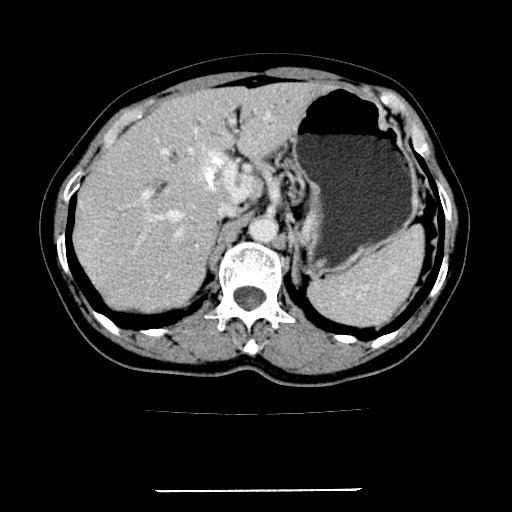

标题: CT22301:女,67岁,上腹部疼痛一周伴皮肤黄染,无发热。 [打印本页]

女,67岁,上腹部疼痛一周伴皮肤黄染,无发热。

左叶肝内胆管结石,并远端肝内胆管扩张。

考虑:肝内胆管结石继发肝内胆管扩张,右肾旋转不良。

肝内外胆管结石并肝内胆管扩张。

肝内外胆管扩张,左叶胆管内结石

建议薄层观察,除外肝门部胆管细胞癌

考虑肝胆管癌;胰头占位?【形态失常,体积增大】

1、肝门高密度影下层面和胰头层面可见轻度胆管扩张,而静脉和延迟期均未见扫描完胰头,不能完全排除胰头占位。2、肝门部高密度影,考虑钙化或结石。

考虑肝门胆管癌伴门脉左支受侵包埋,建议mrcp进一步检查。